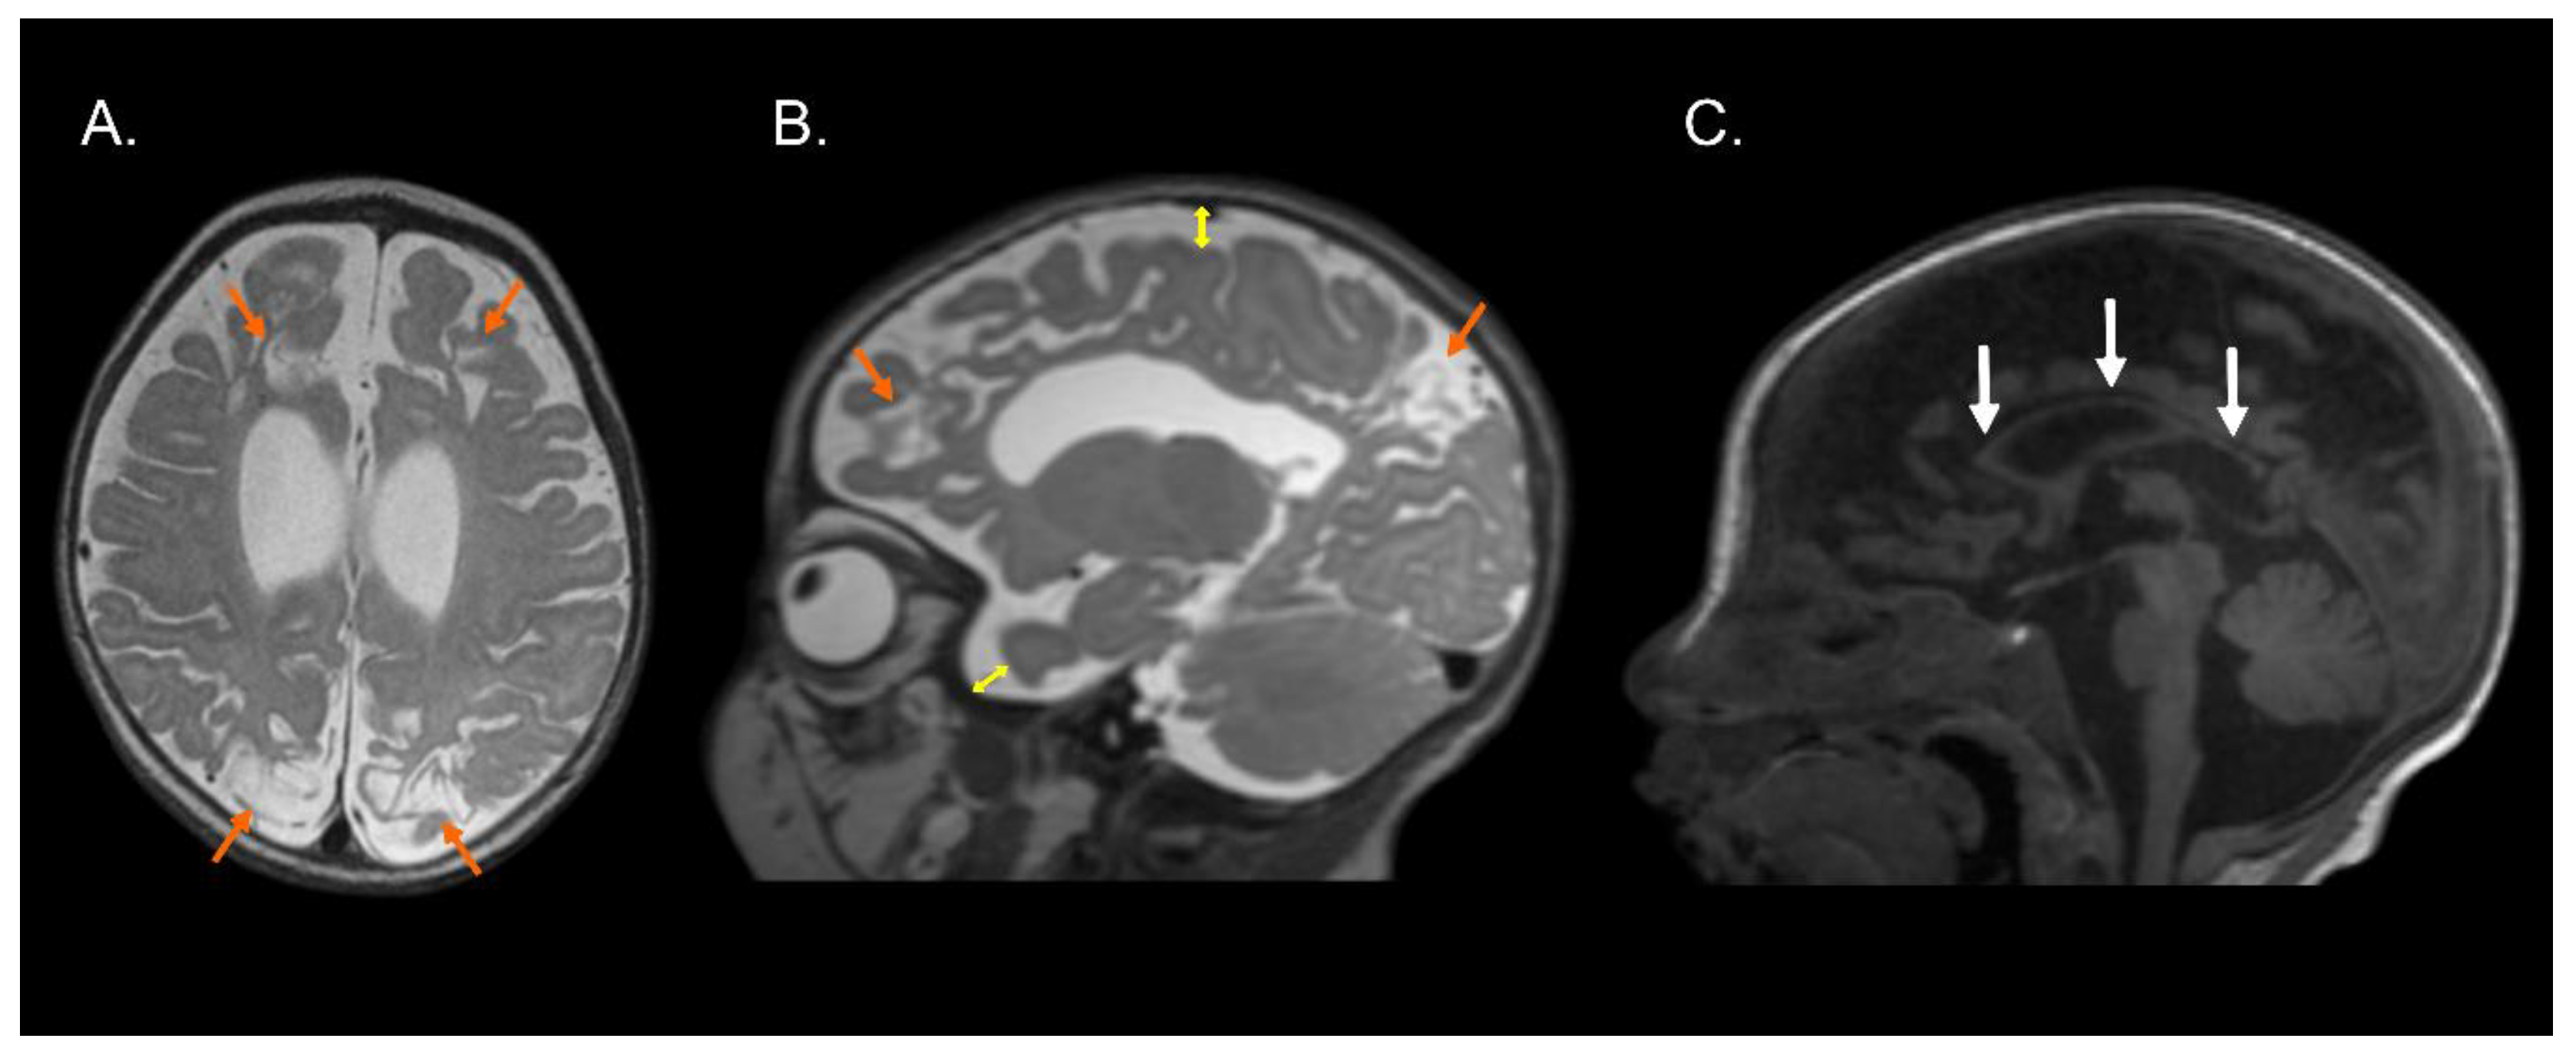

Figure 1, Figure 2 and Figure 3 show the MRI of three infants at the beginning of Katona’s treatment.

Figure 3.

Structural MRI of preterm infant (born at 36 gestational weeks) with a diagnosis of perinatal hypoxic-ischemic encephalopathy. T2-weighted axial (A) and sagittal (B) images and T1-weighted sagittal image (C) exhibiting bilateral parasagittal encephalomalacia in fronto-parieto-occipital region (orange arrows), dilated lateral ventricles, augmented subarachnoid space in the fronto-temporo-parietal region (double direction yellow arrows), and hypoplasia of the corpus callosum (white arrows). Images compatible with parasagittal cerebral injury or “watershed injury”. Images in radiological convention.